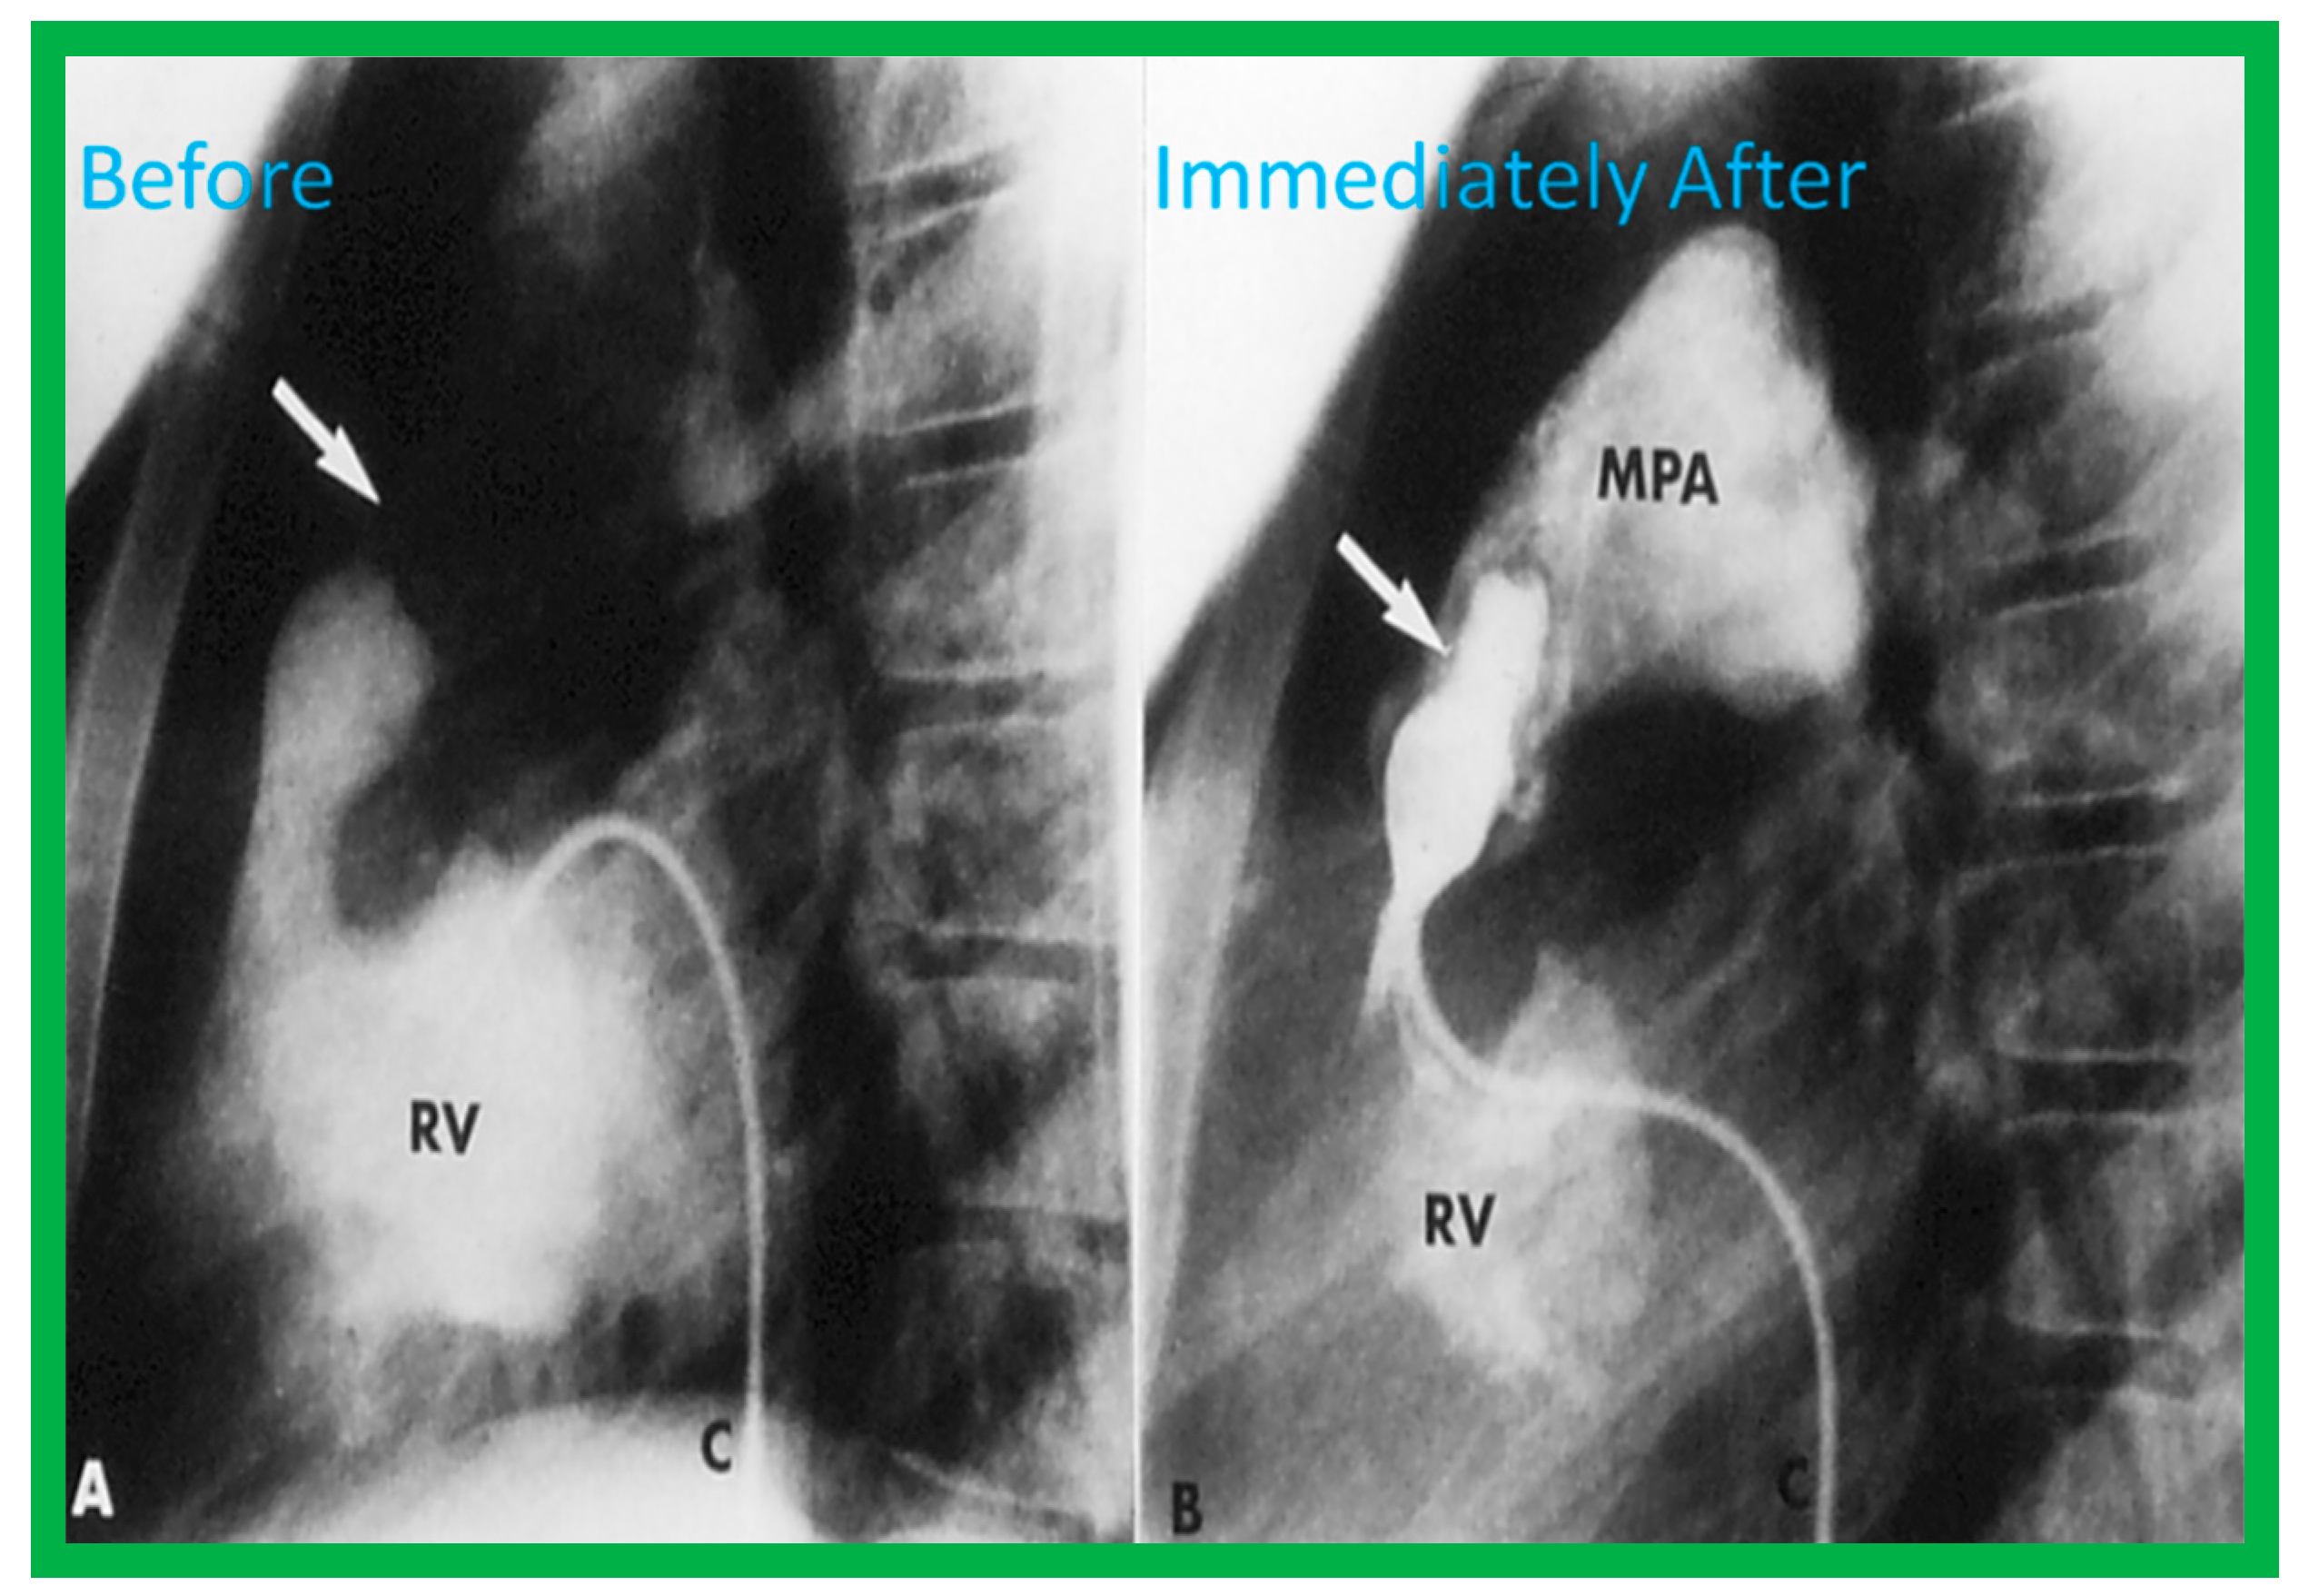

4.1. Pulmonary Stenosis

Pulmonary Stenosis in the Fetus